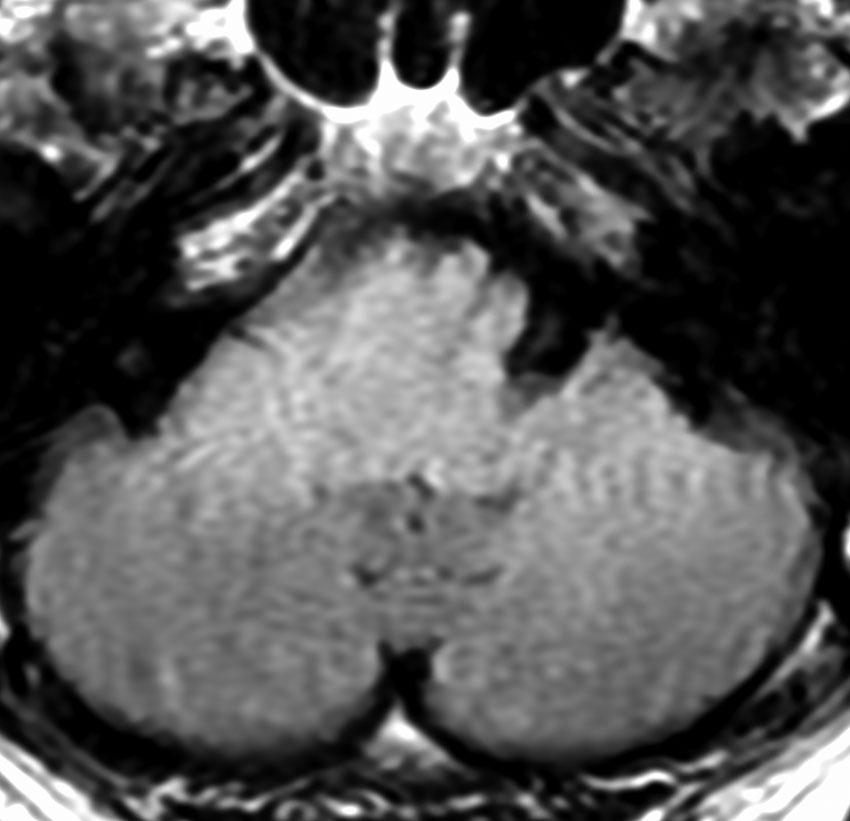

MRI画像所見 60代で嚥下障害と構音障害で発症した例

延髄から中脳まで腫瘍があって脳幹部が腫れています。この画像ですと,小児のびまん性橋膠腫(DIPG,びまん性正中グリオーマ)のように見えます

両側視床から大脳基底核,両側大脳半球深部白質,脳梁まで広範囲に腫瘍が存在します。退形成性星細胞腫のようにまだらにガドリニウム増強されます。